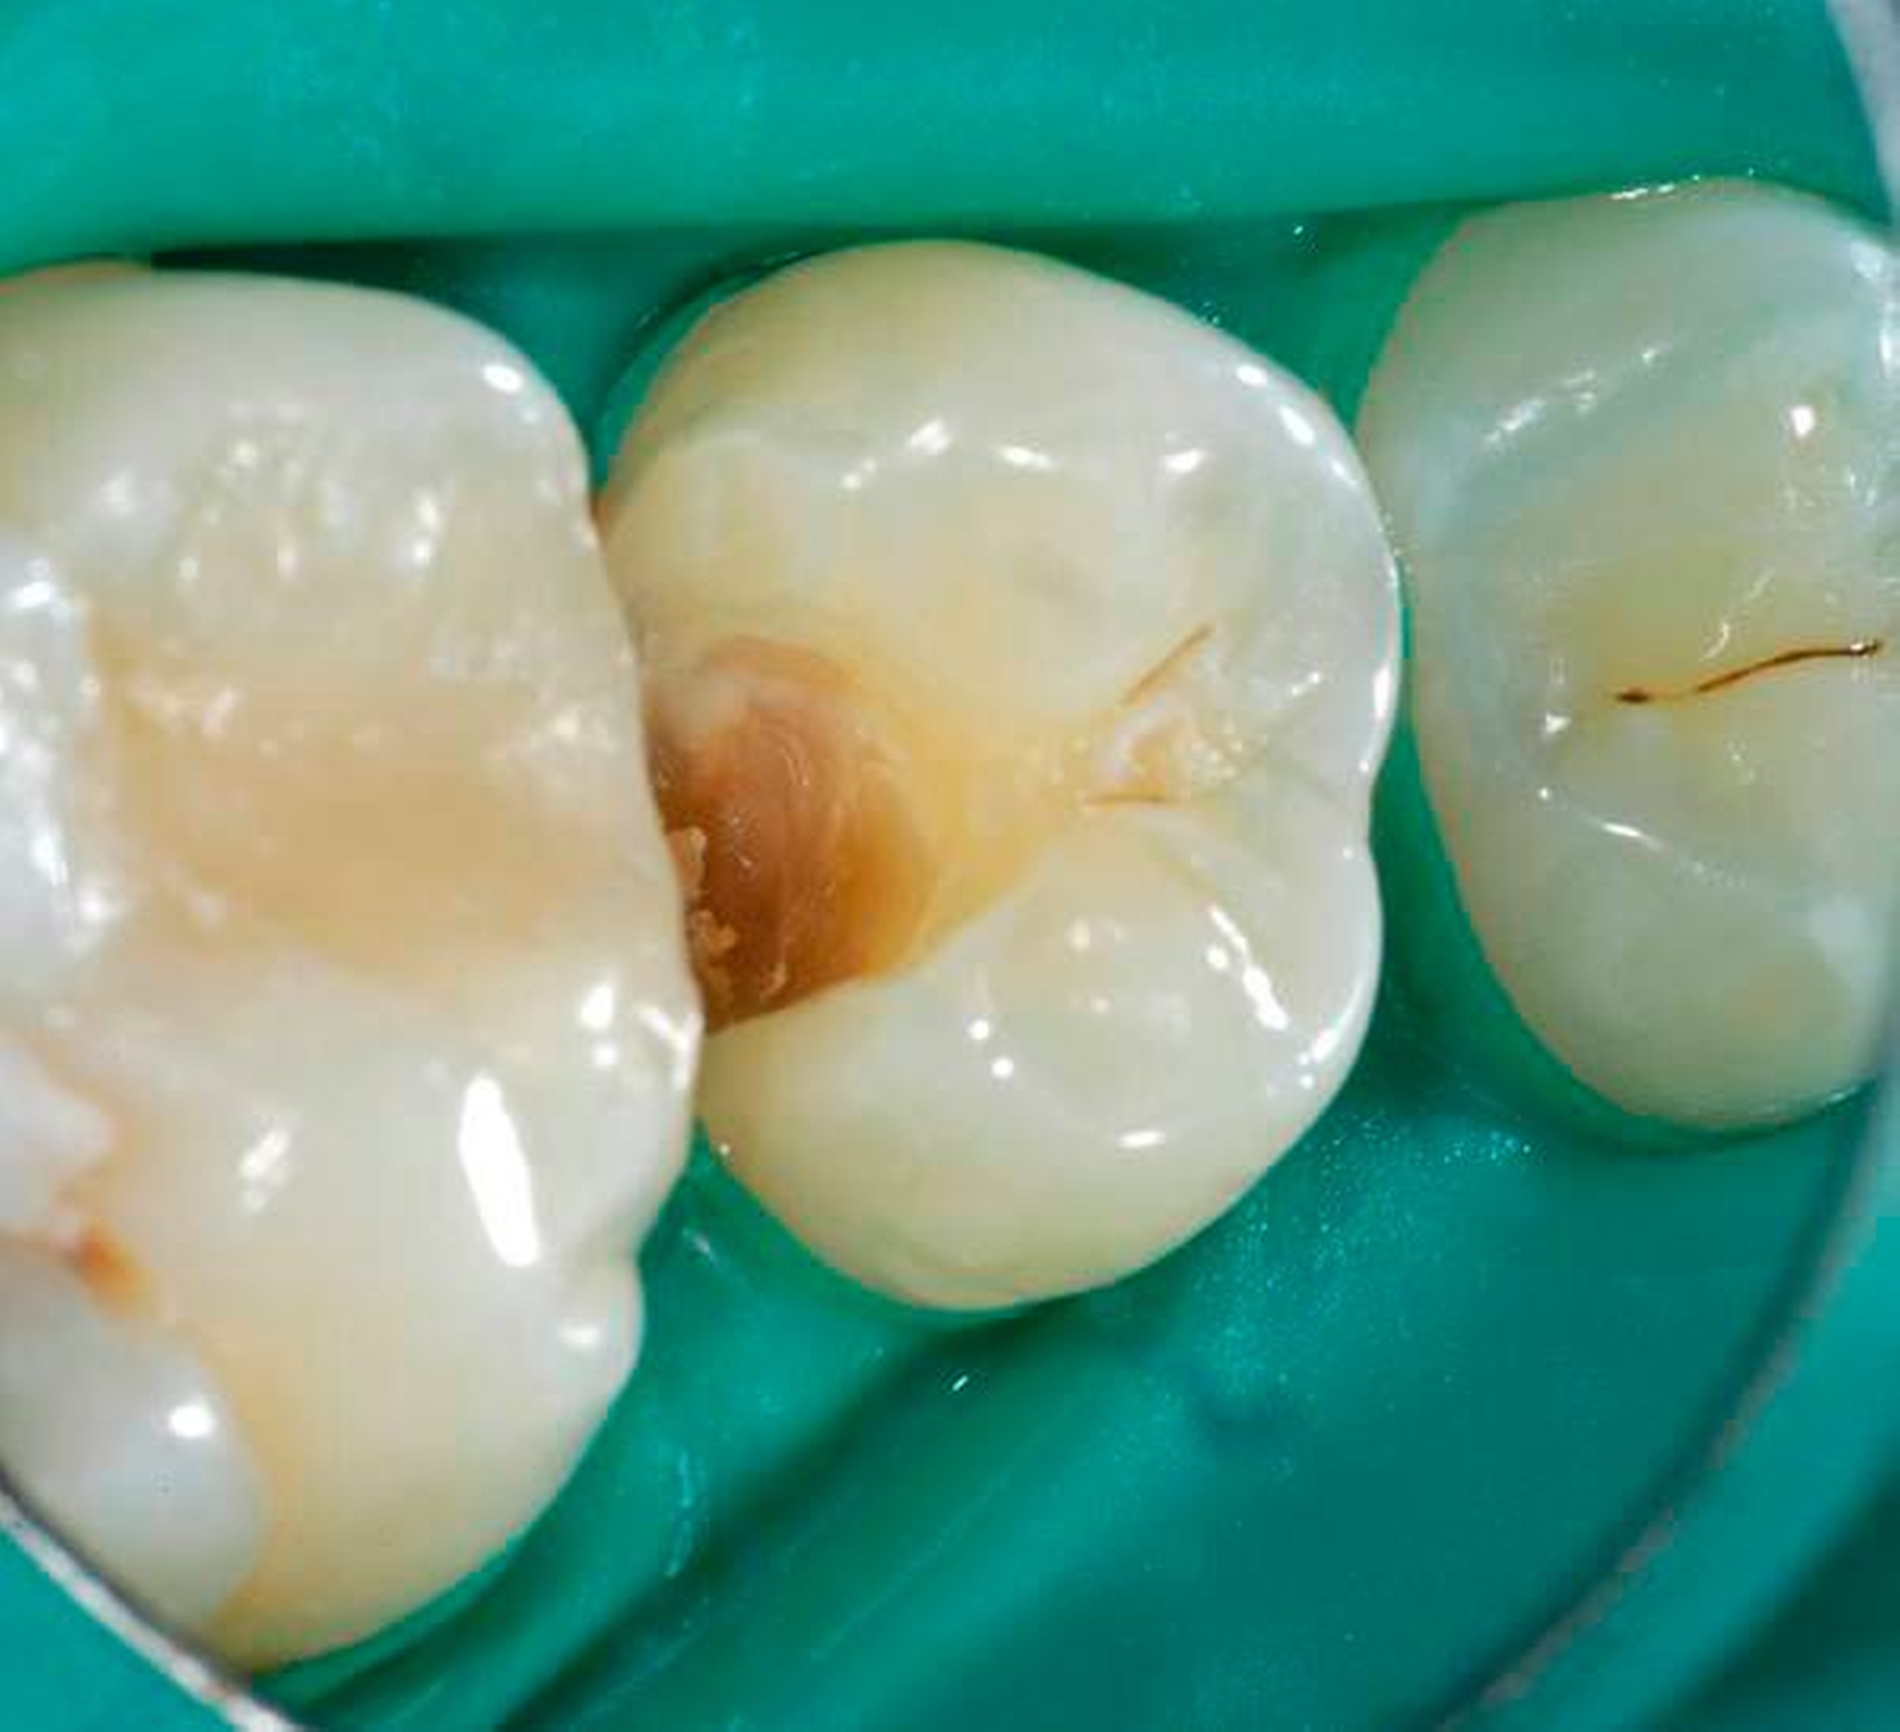

Nachgewiesenermaßen können Calciumsilikat-Zemente die Pulpa zur Bildung von Hartgewebe (Tertiärdentin) stimulieren und sind daher für die Versorgung tiefer kariöser Defekte nach Exkavation und somit für die Vitalerhaltung der Pulpa sehr gut geeignet [15, 21]. Nach indirekter Überkappung mit Biodentine kommt es reproduzierbar zur Ausheilung einer reversiblen Pulpitis [45]. Auch wenn mehr klinische Langzeitstudien zur Vitalerhaltung der Pulpa mit Calciumsilikat-Zementen wünschenswert sind, scheinen nach bisheriger Datenlage Calciumsilikat-Zemente für die indirekte Überkappung der Pulpa besser geeignet zu sein als Calciumhydroxid [2]. Für die direkte Überkappung wurde nachgewiesen, dass Calciumsilikat-Zemente zu besseren klinischen Ergebnissen und höheren Erfolgsraten führt als Calciumhydroxid [50, 60, 63]. Hinsichtlich der Hartgewebebildung ist es dabei unerheblich, ob man ein MTA-Zement oder Biodentine verwendet. Beide Arten von Calciumsilikat-Zement führen beim Menschen zu einer identischen Hartgewebsbrückenbildung [68] (Abbildungen 3 bis 10).